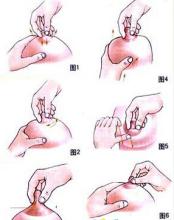

产后美乳不偷懒产后乳房变形完全属于正常的生理变化,在怀孕的时候,母体为了做好哺乳的准备,因此乳...

产后美乳不偷懒产后乳房变形完全属于正常的生理变化,在怀孕的时候,母体为了做好哺乳的准备,因此乳... -